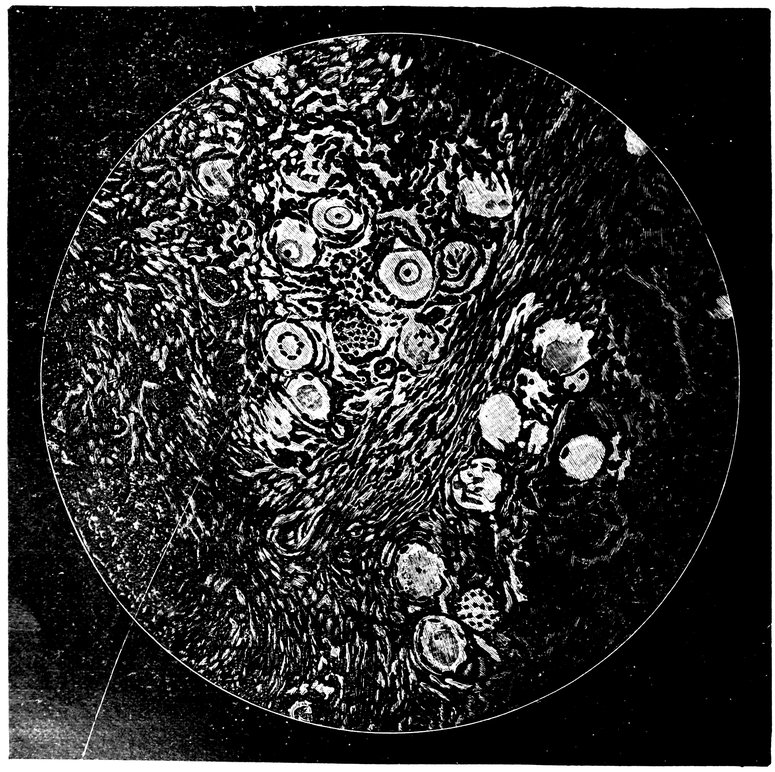

| 15. | Primitive follicles | 58 |

| 16. | Ripening follicles | 61 |

| 17. | Graafian follicles | 62 |

| 84. | Sagittal section through the ovary of a girl aged sixteen | 583 |

| 85. | Sagittal section through the ovary of a woman aged seventy-two years | 584 |

| 86. | Diagrammatic Representation of the Graafian Follicle | 585 |

We must first consider the changes in the ovaries, which play an etiologically important part. At the onset of puberty, the follicular masses of the ovary exhibit a more active growth, the follicles increase in size, with their contained ova they approach the surface, and finally, by the bursting of the follicles, the ova are extruded. Then, in the life-phase in which conception occurs, and under the influence of the hyperæmia of all the pelvic viscera that accompanies this process, a notable development of the corpus luteum takes place, this latter body reaching its maximum size in the eleventh week of pregnancy, subsequently undergoing involution and leading to the formation of a considerable scar. Finally, in the critical period of life in which the menstrual flow ceases, a continually increasing growth and new formation of connective tissue-stroma takes place in the ovaries at the expense of their cellular constituents, and a regressive metamorphosis of the graafian follicles occurs.